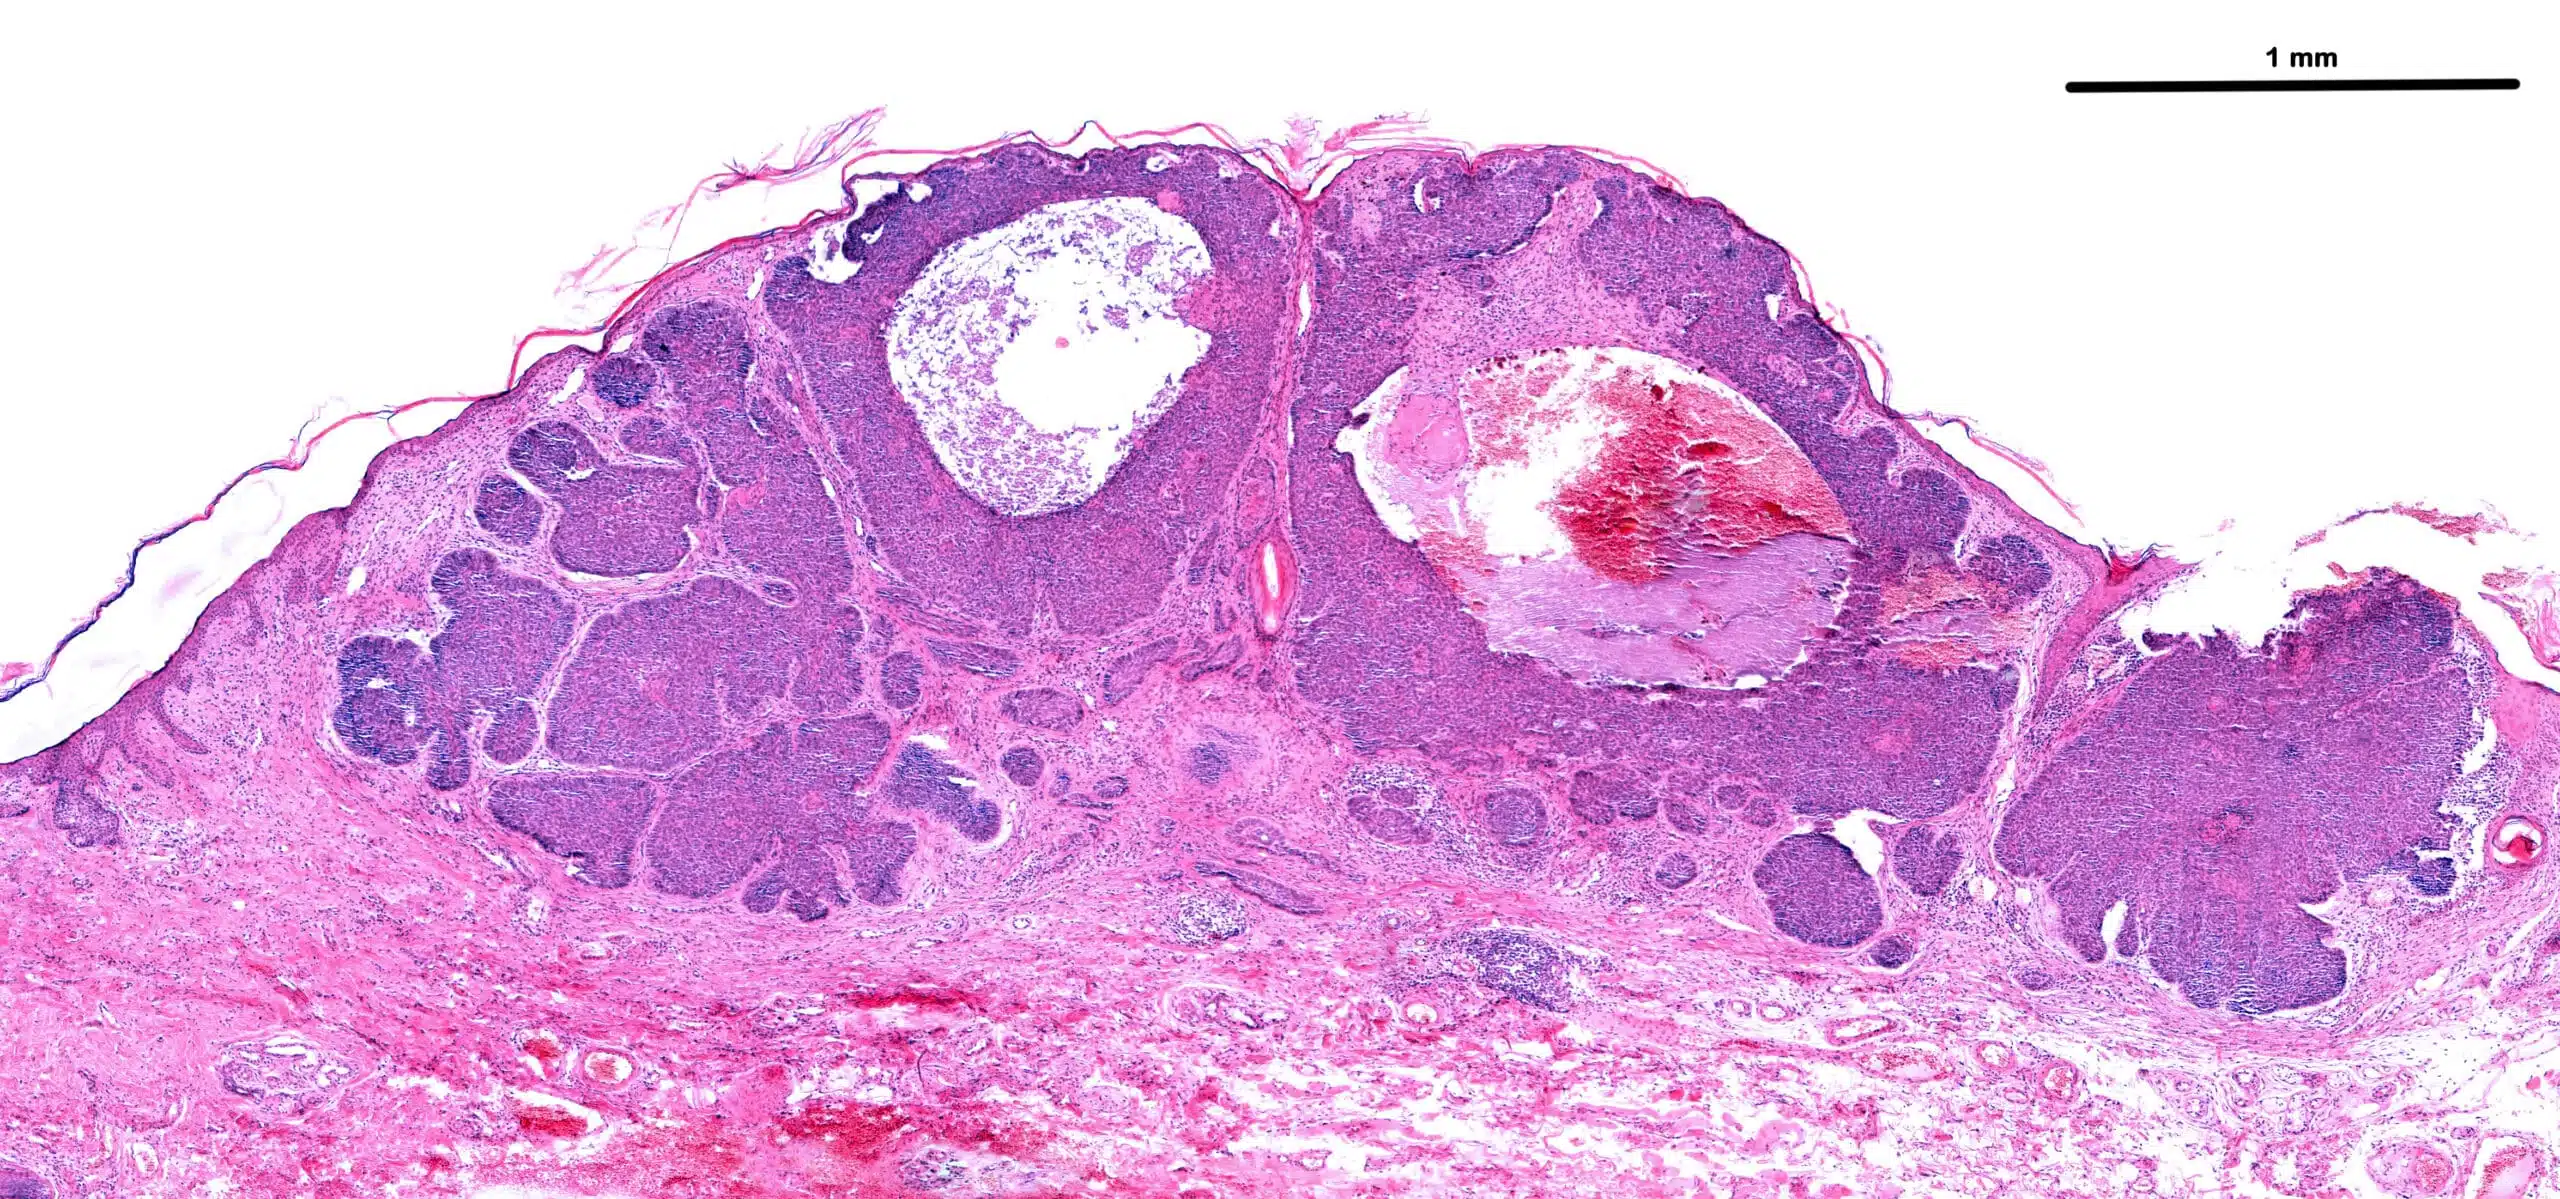

Large,Basal,Cell,Carcinoma.,Cords,And,Large,Islands,Of,Basophilic

Anatomic Pathology

We’re committed to delivering gold-standard tissue sourcing, processing and analysis services.